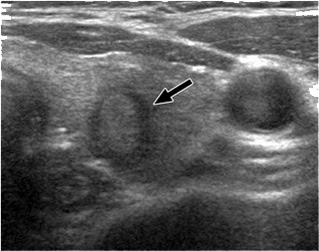

Ακόμα και όταν η βιοψία θυρεοειδούς δείξει καλοήθεια, το μέγεθος του όζου θα πρέπει να παρακολουθείται. Το υπερηχογράφημα παρέχει αντικειμενικό και ακριβή τρόπο ανίχνευσης μεταβολών στο μέγεθος του όζου. Ένας καλοήθης όζος (από τη βιοψία) που παραμένει σταθερός σε μέγεθος ή που φαίνεται να μικραίνει σε διαδοχικά υπερηχογραφήματα, δεν είναι πιθανό να είναι κακοήθης και να απαιτεί χειρουργική αφαίρεση. (Εικόνα Β, Γ).

Εικόνα Β (Φυσιολογικός θυρεοειδής αδένας σε υπερηχογράφημα)

Εικόνα Γ (Συμπαγής όζος στον αριστερό λοβό του θυρεοειδούς σε υπερηχογράφημα)